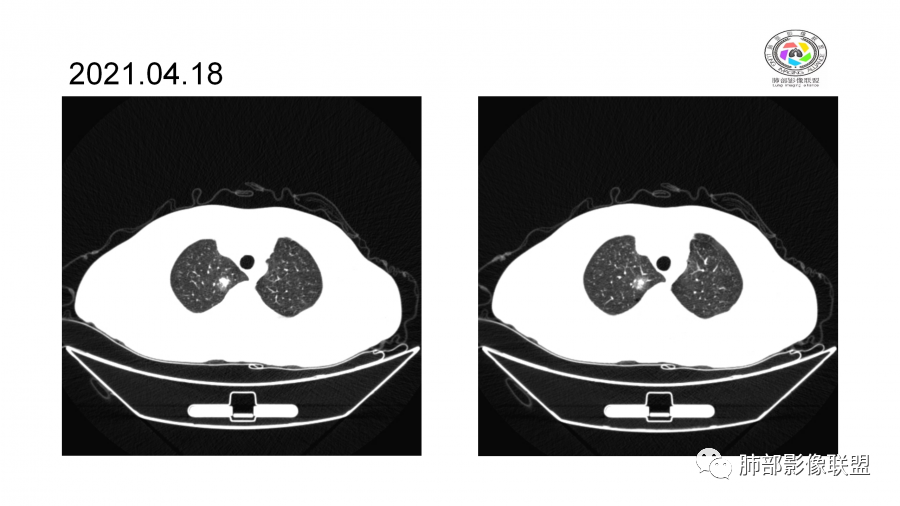

中年男性,高血压,肾功能衰竭,贫血病史,尿潜血阳性。3.8双肺野多发斑片磨玻璃实变影,结节影,边缘模糊,周围有晕征,内见支气管充气征,主要沿支气管血管束分布,部分胸膜下分布,3.12号病灶有吸收好转,4.8号斑片实变影基本吸收,主要沿支气管血管束分布结节影,边缘平直收缩,4.28病灶大部分吸收好转,双肺支气管血管束增粗,有少量结节影。考虑ANCA相关性血管炎可能性大,第一次片子觉得隐球菌不排除,但是后面没有抗真菌治疗就吸收了,觉得隐球菌可能性不大。

胸部CT:双肺多发实性斑片影,散在GGO。实性斑片周围可见晕征、边缘模糊不清,病灶于肺外围区域优势分布。肺门区血管影增粗,支气管套袖,目测肺动脉增粗。3月、4月复查肺内实性斑片病灶呈游走性,此起彼伏。

10天后:病灶继续吸收好转

伴随少量胸水

应该与气道无关

符合间质、血管来源病变

此起彼伏